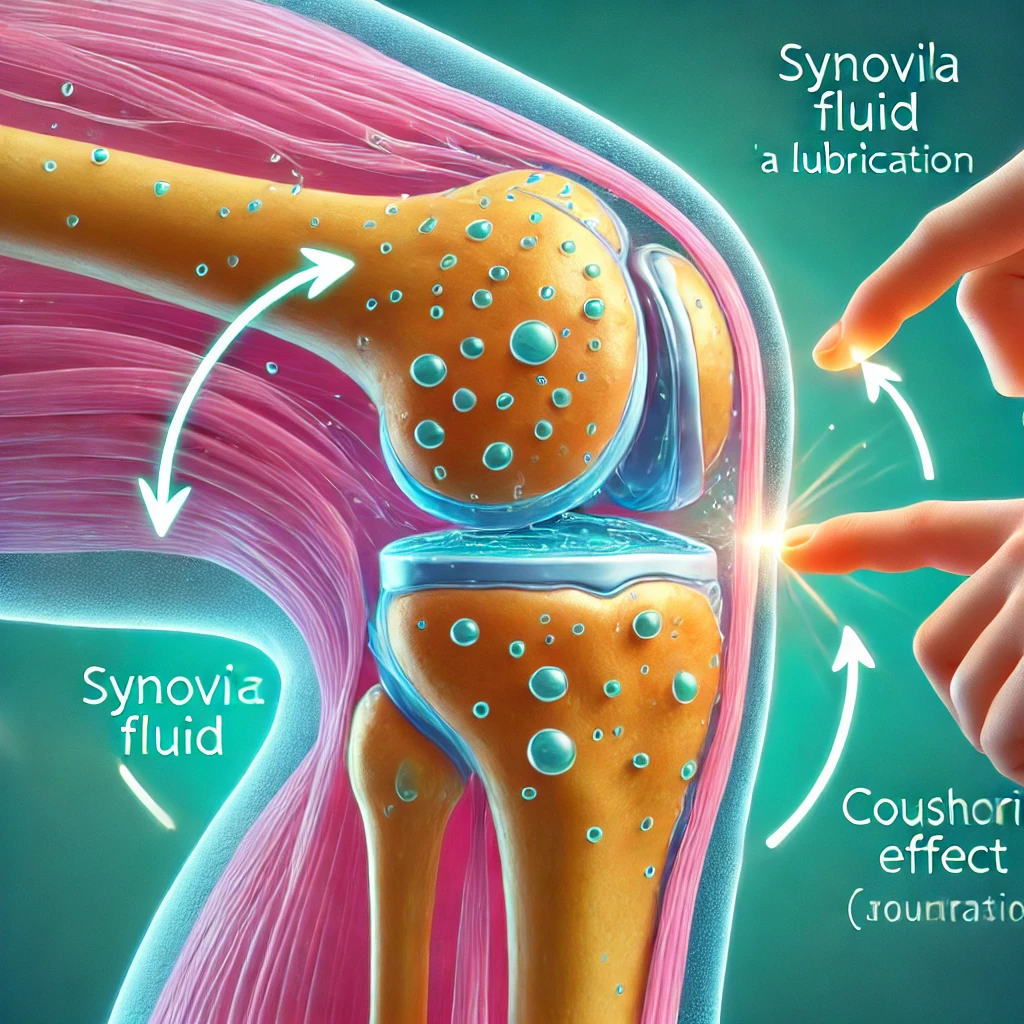

관절의 윤활제 역할

콘드로이친은 관절의 윤활제 역할을 하여 관절의 움직임을 부드럽게 만듭니다. 이는 특히 나이가 들면서 관절이 뻣뻣해지는 중장년층에게 큰 도움이 됩니다.